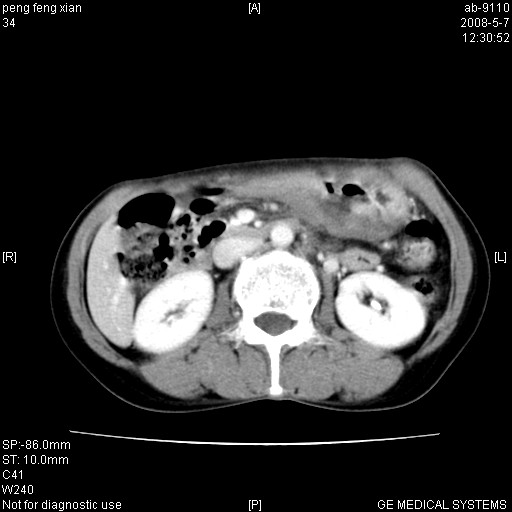

女,56岁。b超左一腹包块,考虑胃肠道肿瘤。

结肠病变?建议行全消化道检查!

胃癌并转移。